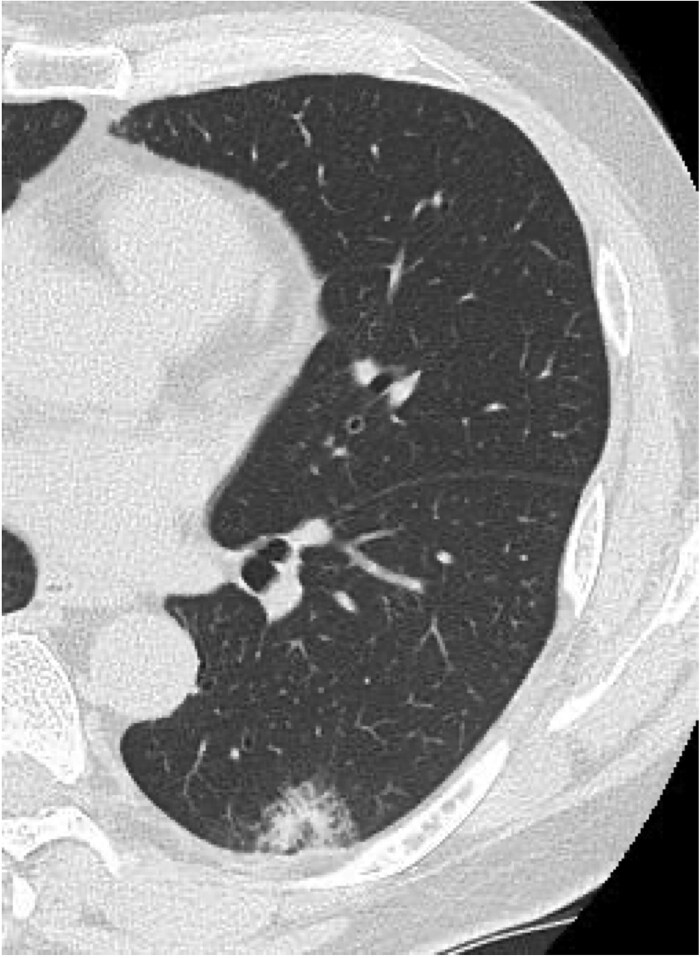

迟发性组织性肺炎作为急性冠状病毒病2019 (COVID-19)综合征的表现在围手术期尚未见文献记载。这里,一位61岁的男性接受了左下肺叶切除术,并伴有持续的漏气,需要进行7次胸膜切除术。患者于术后第10天感染COVID-19,最初恢复,但于第27天再次入院,出现发烧和呼吸衰竭。胸部计算机断层扫描显示进行性实变伴磨玻璃影。最初的甲基强的松龙脉冲治疗反应有限,需要第二个疗程加环孢素a。患者在术后第104天获得了明显的放射学改善。根据两期临床病程、独特的影像学进展和有限的类固醇反应,诊断为急性后COVID-19综合征继发迟发性肺炎。该病例强调了对肺切除术后COVID-19患者进行延长监测的重要性,以便及早发现并及时干预延迟性肺部并发症。

Delayed-onset organizing pneumonia as a manifestation of post-acute coronavirus disease 2019 (COVID-19) syndrome has not been documented in the perioperative setting. Here, a 61-year-old man underwent left lower lobectomy complicated by persistent air leakage requiring seven pleurodesis procedures. He developed COVID-19 on postoperative Day 10 and initially recovered but was readmitted on Day 27 with fever and respiratory failure. Chest computed tomography revealed progressive consolidations with ground-glass opacities. Initial methylprednisolone pulse therapy showed limited response, necessitating a second course with cyclosporine A addition. The patient achieved substantial radiological improvement by postoperative Day 104. Based on the biphasic clinical course, distinctive radiological progression, and limited steroid response, delayed-onset organizing pneumonia secondary to post-acute COVID-19 syndrome was diagnosed. This case highlights the importance of extended monitoring in post-lung resection patients with COVID-19 to enable early recognition and prompt intervention of delayed pulmonary complications.